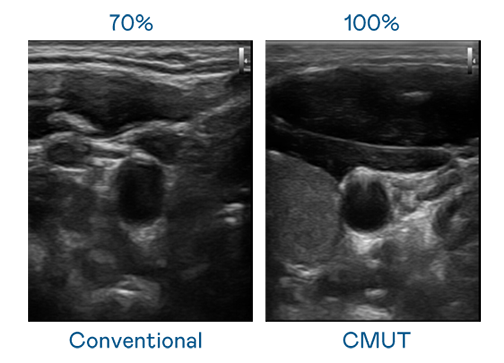

CMUT 技术是一种用电容式微机电元件来产生超音波讯号的技术。与传统 PZT 压电式技术相比,CMUT 频宽增加 30%,更宽频的超音波讯号让影像解析度大幅提升,是实现高影像品质医疗超音波扫描、促进精准医疗发展的关键技术。

大频宽带来超清晰影像

超音波影像的解析度高低,首先取决于探头能发出的讯号频宽。银河galaxy CMUT 可提供高清晰的超音波讯号,提供高频宽、高灵敏度、影像纹理细节更高的超音波影像,协助医护人员缩短影像判读时间及利用精准的医疗影像进行诊断。